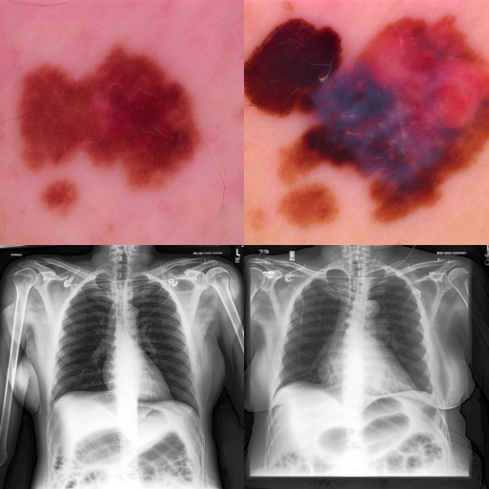

A key advantage of diffusion classifiers lies in their intrinsic interpretability, which positions diffusion classifiers as not only effective but also transparent. Importantly, diffusion classifiers are able to produce counterfactual explanations, as opposed to other interpretability methods that simply highlight regions of interest. This can be seen in Figure 3: On the left example (skin lesion), the counterfactual of a malignant lesion (melanoma) has changed colour and intensity to become healthy. In the right example (chest X-ray), the counterfactual image of a sick patient (pleural effusion) shows decreased disease pathology in the left and right lungs. The natural interpretability of diffusion classifiers provides both transparency on how the model is learning (thus allowing the identification of shortcut learning), and specific class information which improves understanding of the disease. In addition to providing disease explainability, the difference maps also reveal how the model makes its decision: the condition with the least reconstruction error is selected as the predicted class.

Refer to caption

Figure 3: Diffusion classifiers are naturally explainable and highlight why they make classification decisions using classifier-free guided sampling. Difference maps show conditional areas of interest (pathology added/removed) during reconstruction.

Appendix E More Explainability Results

More explainability results can be found in Figure 6, and Figure 7. Input sick images have been altered to healthy class by adding noise to the input image and denoising with the healthy class. For CheXpert t=0.5 and for ISIC t=0.3 are used. CFG scale is 7.5.

Figure 7: More explainability results for ISIC by converting input sick images to healthy images. t=0.3 and CFG=7.5 are used for generating these images.